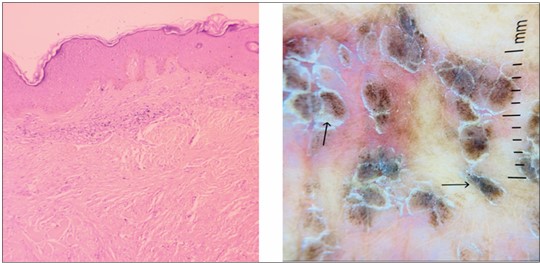

Annular Keloid Mimicking Granuloma Annulare: A Diagnostic Challenge

Ghoghara P, Dhanani S, Nair PA. Annular keloid mimicking granuloma annulare: a diagnostic challenge. RFP J Dermatol. 2025;10(2):47-9.